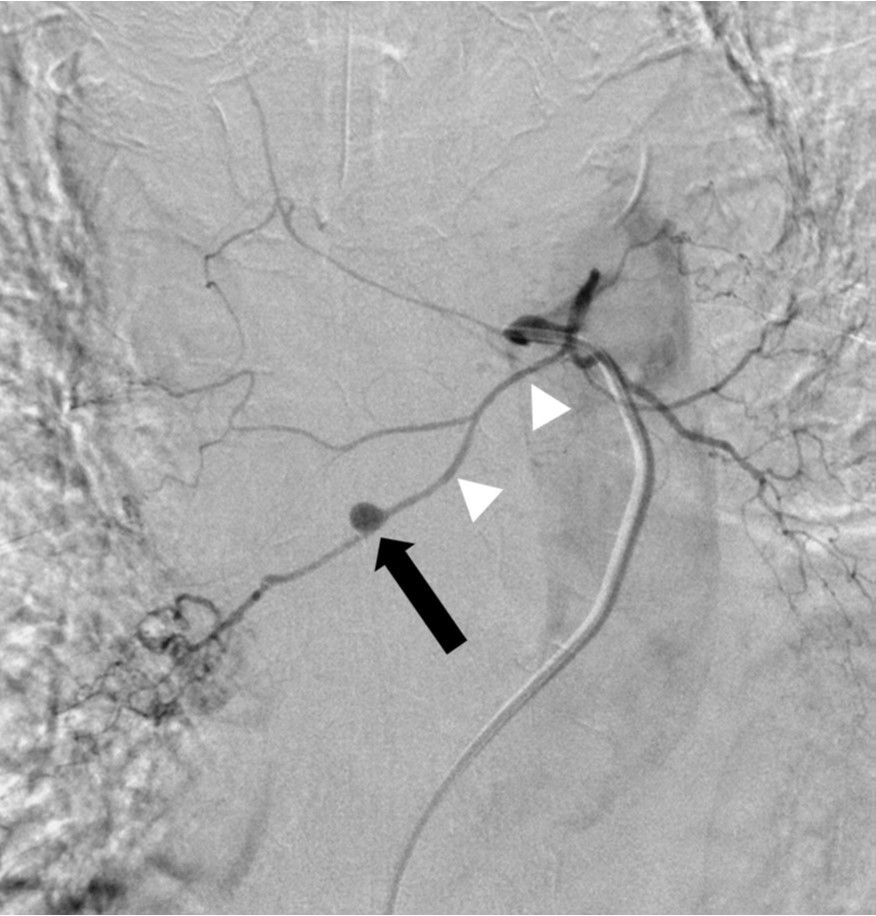

Fig. 3A, B. Thoracic aortogram (A) shows a small aneurysm (arrow) in the mid-thorax. Common bronchial arteriogram (B) reveals that the aneurysm (arrow) is located at the mid-portion of the right bronchial artery (arrowheads).